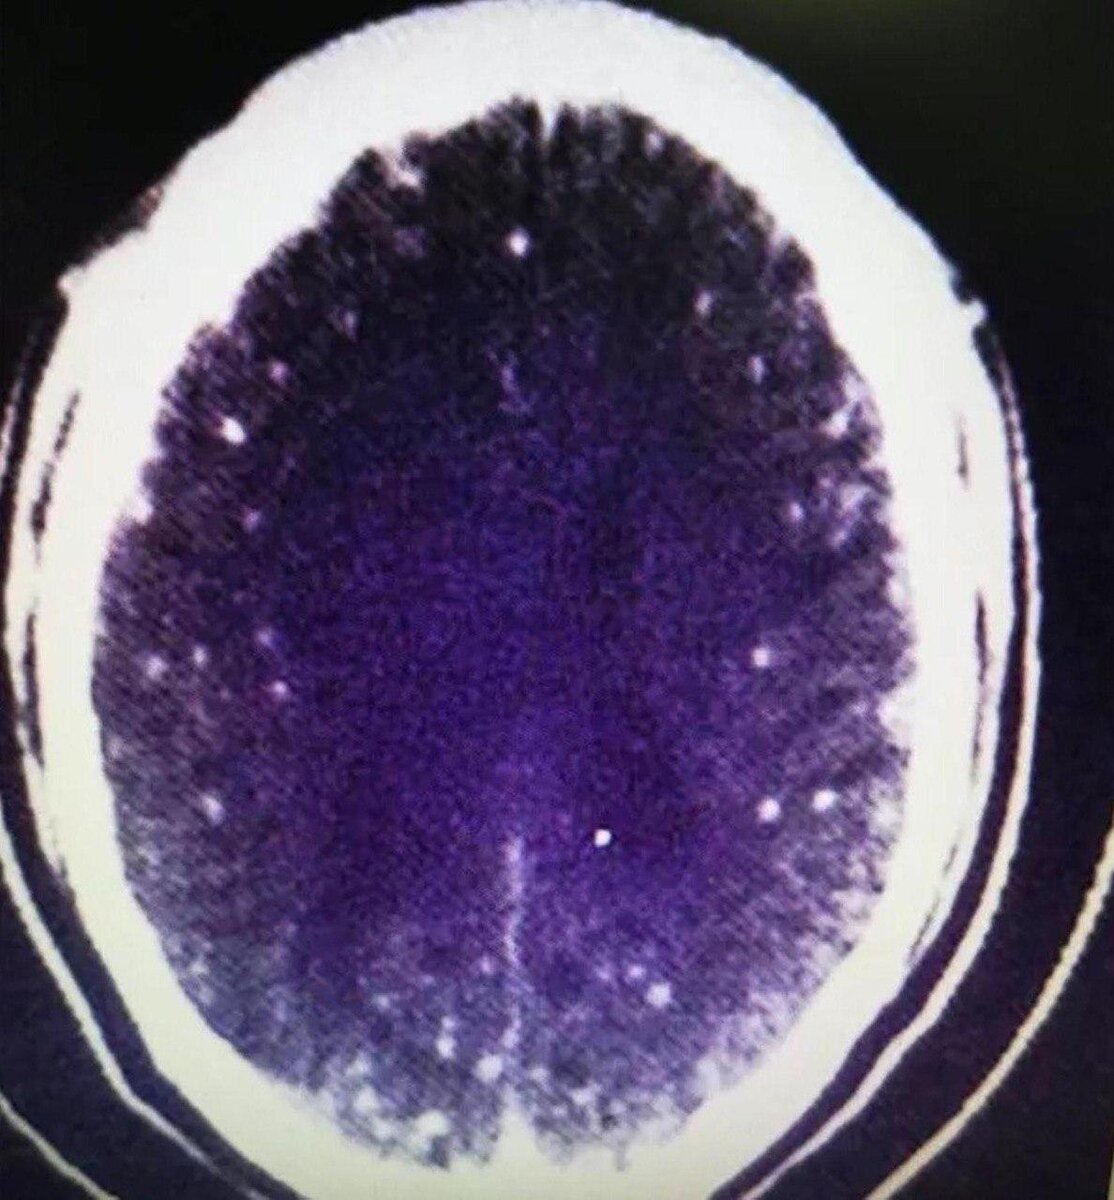

В любом школьном учебнике по зоологии написано: не ешьте сырое и непрожаренное мясо, если не уверены, что в нем нет паразитов. Тем не менее, в мире еще есть люди, которые не следуют этому простому правилу. Так, один китайский строитель начал внезапно испытывать тошноту и сильные головные боли, но не придал этому большого значения. В больнице он оказался после того, как у него случился эпилептический припадок прямо на работе и коллеги вызвали ему скорую помощь. Проведя подробное обследование врачи обнаружили в мозге пациента не менее 700 личинок свиного цепня. Именно они, судя по всему, и стали причиной всех его симптомов. В разговоре с врачами он вспомнил, что незадолго до появления симптомов тушил мясо в красном соусе, и из-за этого не смог разглядеть, получилось ли приготовить его до конца.

Проведя подробное обследование врачи обнаружили в мозге пациента не менее 700 личинок свиного цепня. Именно они, судя по всему, и стали причиной всех его симптомов. В разговоре с врачами он вспомнил, что незадолго до появления симптомов тушил мясо в красном соусе, и из-за этого не смог разглядеть, получилось ли приготовить его до конца.